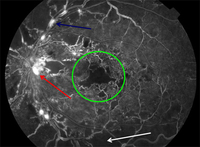

Fluorescein angiography in proliferative diabetic retinopathy: new vessels elsewhere (red circle), capillary non-perfusion (white arrow), pan-retinal laser burns (blue arrow)

Courtesy of Moorfields Photographic Archive; used with permission